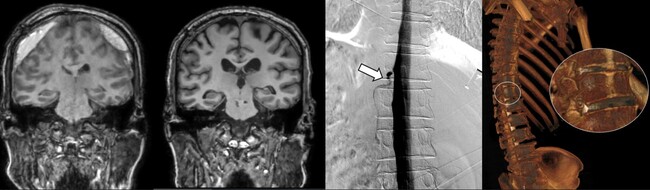

DSM과 더불어 세브란스병원이 함께 진행 중인 측위 컴퓨터단층촬영(CT) 척수조영술까지, 모두 뇌척수액 정맥 누공을 진단할 수 있는 최신 기법이다. 뇌척수액 누출로 위축된 뇌(맨 왼쪽), DSM으로 확인한 누공 위치(세번째), 측위 CT 척수조영술로 확인한 뇌척수액 정맥누공 3D 영상(오른쪽)

이번에 세브란스병원을 찾은 환자들은 DSM 검사와 측위 CT 척수조영술로 뇌척수가 새어나가는 부위를 정확히 진단‧치료받고, 뇌압을 회복했으며 경막하출혈도 사라졌다. 이에 따라 환자들이 보였던 인지기능 저하와 보행장애도 모두 호전됐다.

하우석 교수는 “자발성 두개내압 저하증과 특별한 외상이 없이 발생하는 경막하출혈의 원인 중 하나였던 뇌척수액 척수 누공은 두통, 인지능력 저하 등 심각한 고통을 일으키지만, 기존 진단법으로는 원인 규명이 쉽지 않던 상황”이라며 “다학제 진료와 세브란스병원이 도입한 DSM과 측위 CT 척수조영술로는 척수액 누출이 발생하는 지점을 정확히 찾아내 치료할 수 있다”고 말했다.